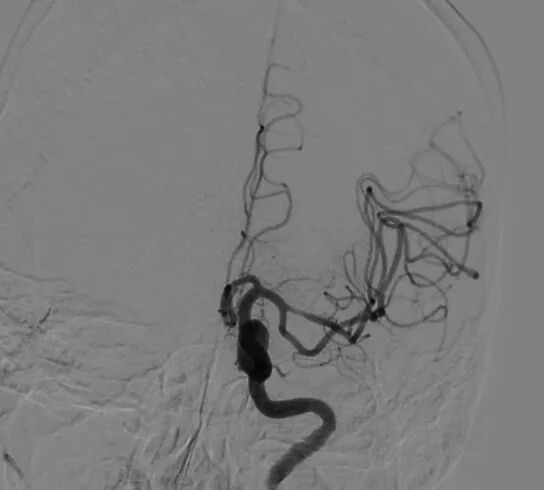

术前图示。

专家团队注意到,刘老太太除了93岁高龄,还伴有心功能不全、肾功能不全等基础疾病,手术风险高于一般患者,且闭塞血管是关键供血动脉,若不及时开通,将导致永久性残疾甚至生命危险。与家属充分沟通并获得支持后,团队果断确定施行“DSA脑血管造影+介入血管内取栓术”。

手术术后图示:行“左侧大脑中动脉M1段取栓再通术后”血流通畅。

在多学科团队的密切配合下,综合介入科主任副主任医师吴鉴洲带领手术团队迅速就位。通过大腿根部微创穿刺,在DSA实时引导下将取栓支架精准送达闭塞部位,仅一次操作便成功取出完整血栓。术后造影显示,血管恢复通畅,大脑血流灌注立刻改善。从家属签字到血管再通,全程仅用20分钟,一场高效的“脑部血管疏通战”顺利完成。